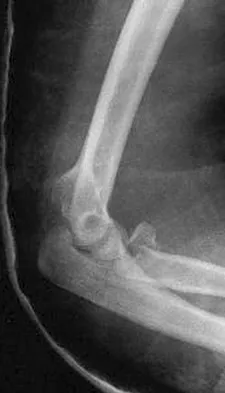

Figure 27 shows the radiograph of a 26-year-old man who sustained a closed head injury and a closed elbow dislocation 6 weeks ago. Examination reveals 65 degrees to 115 degrees of flexion, and intensive physical therapy has resulted in no improvement. A decision regarding the timing of surgical correction of the contracture should be based on

The patient has heterotopic ossification, a more common finding in patients who have sustained head injuries. Treatment will require removal of the heterotopic bone and anterior and posterior capsulectomies. The main concern about timing is the possible recurrence of heterotopic bone. While an extended wait was once thought necessary, this is no longer true. The timing is based on the time since injury and evidence of bone maturation on plain radiographs. A sharp marginal demarcation of the new bone and a trabecular pattern within it are usually present 3 to 6 months after onset, indicating that it is safe to proceed with surgical excision. It is not necessary to wait more than 6 months. Bone scan results are not good indicators because they may remain "hot" for long periods of time. The levels of alkaline phosphatase and serum calcium-phosphorus product do not need to be measured.